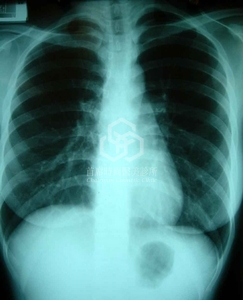

這還沒什麼, 您知道更驚人的是, 她還有脊柱側彎的問題呢! 等於"雙效合一", 難怪胸部大小不一(如下圖).

@@ 脊柱側彎 (Scoliosis)

脊柱側彎的發生率為2-3%, 男女好發比率約為1:10, 也就是大都是女性. 大都是原因不明(佔80%), 也就是自發性(idiopathic). 好發明顯於生長快速的青春期年紀(12到13歲或國小五六年級左右), 由於是漸進式惡化, 所以小時候學齡時, 父母親必須多加留意, 通常可以防止惡化, 尤其是背負過重的書包+鈣質攝取不足必須避免.

這是乳房不對稱最明顯的胸闊主因, 通常整形外科醫師不太認真看消費者的胸部X光, 畢竟美容刀誰管那麼多, 交給麻醉科醫師看就好, 甚至兩個人都不看.

結果其實它透露出許多寶貴的訊息, 非常可惜.